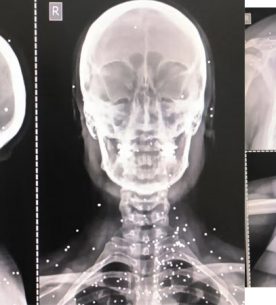

۳۰ بهمن ۱۴۰۴گزارش گاردین از هدفگیری عمدی اعضای حیاتی بدن برای سرکوب معترضان در ایران نشان شجاعت اجلاس ژنو به «قهرمانان ایران» اهدا شد سپاه پاسداران به طور رسمی در فهرست سازمانهای تروریستی اتحادیه اروپا قرار گرفت لهستان... -